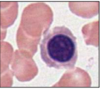

What does Wright’s Stain show?

Complete blood cell counts